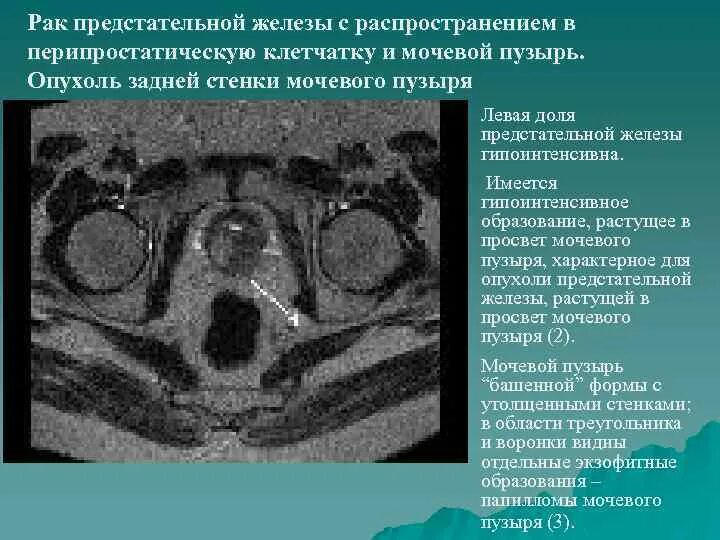

Объемное образование в предстательной железе кт. Местно распространенный

Объемное образование в предстательной железе кт. Местно распространенный Злокачественное Перерождение предстательной железы

Сосудисто нервный пучок предстательной железы. Экстракапсулярная экстензия предстательной железы что это. Лучевая диагностика предстательной железы. Инвазия капсулы предстательной железы Предстательная железа у мужчин. Представительна яжелеза. Опухальпредседательнойжелезы